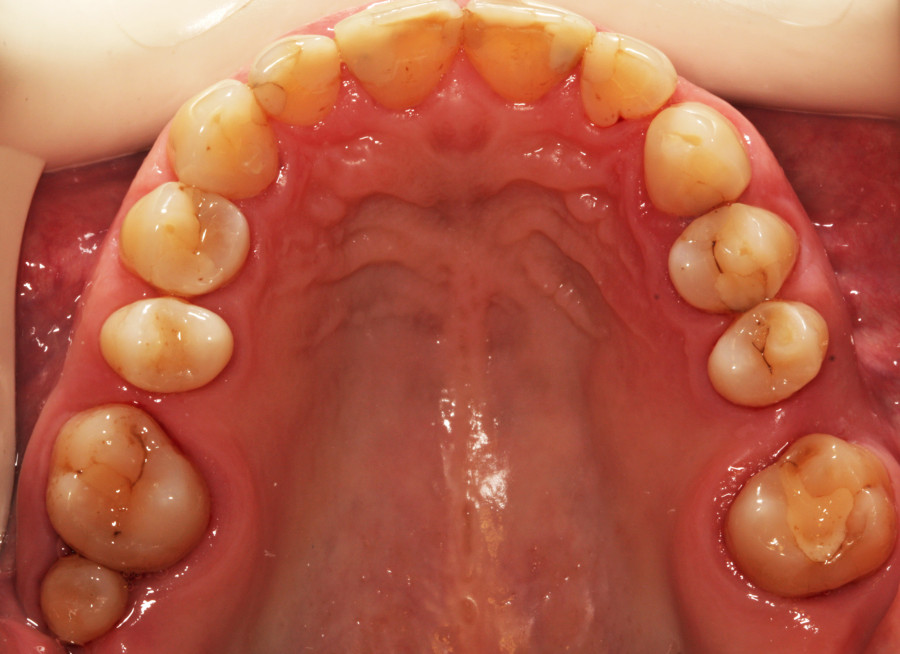

Do kliniki Stomatologia Bez Bólu zgłosiła się pacjentka, lat 61 z problemem nadwrażliwości zębów. Po przeprowadzonym wywiadzie stwierdzono spożywanie sporej ilości sezonowych owoców (truskawki, wiśnie, czereśnie, czarna porzeczka), nawet 3 razy dziennie. Następnie wykonano badanie wewnątrzustne. Stwierdzono obecność płytki nazębnej, ciemnego osadu oraz kamienia nazębnego na części trzonowców: